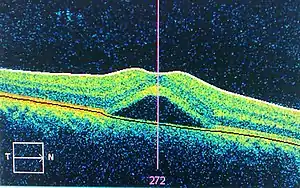

| An occurrence of central serous retinopathy of the fovea centralis imaged using optical coherence tomography. | |

Optical coherence tomography imaging of central serous retinopathy

The diagnosis usually starts with a dilated examination of the retina, followed with confirmation by optical coherence tomography and fluorescein angiography. The angiography test will usually show one or more fluorescent spots with fluid leakage. In 10%-15% of the cases these will appear in a "classic" smokestack shape. Differential diagnosis should be immediately performed to rule out retinal detachment, which is a medical emergency. A clinical record should be taken to keep a timeline of the detachment. The affected eye will sometimes exhibit a refractive spectacle prescription that is more far-sighted than the fellow eye due to the decreased focal length caused by the raising of the retina.